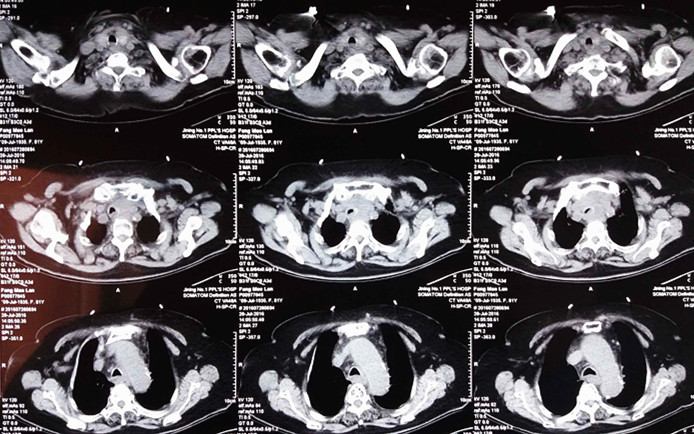

我院呼吸内科为一位高龄患者经支气管镜成功置入气管支架。该患者为一名82岁女性,憋喘重,不能平卧,食道癌放疗后,考虑为食道肿瘤压迫气道,以下为肺部CT所见,可见气管只有一线之隙,重度狭窄。

支架置入后患者憋喘,明显减轻,不仅挽救了患者的生命,更为继续治疗赢得宝贵时间。